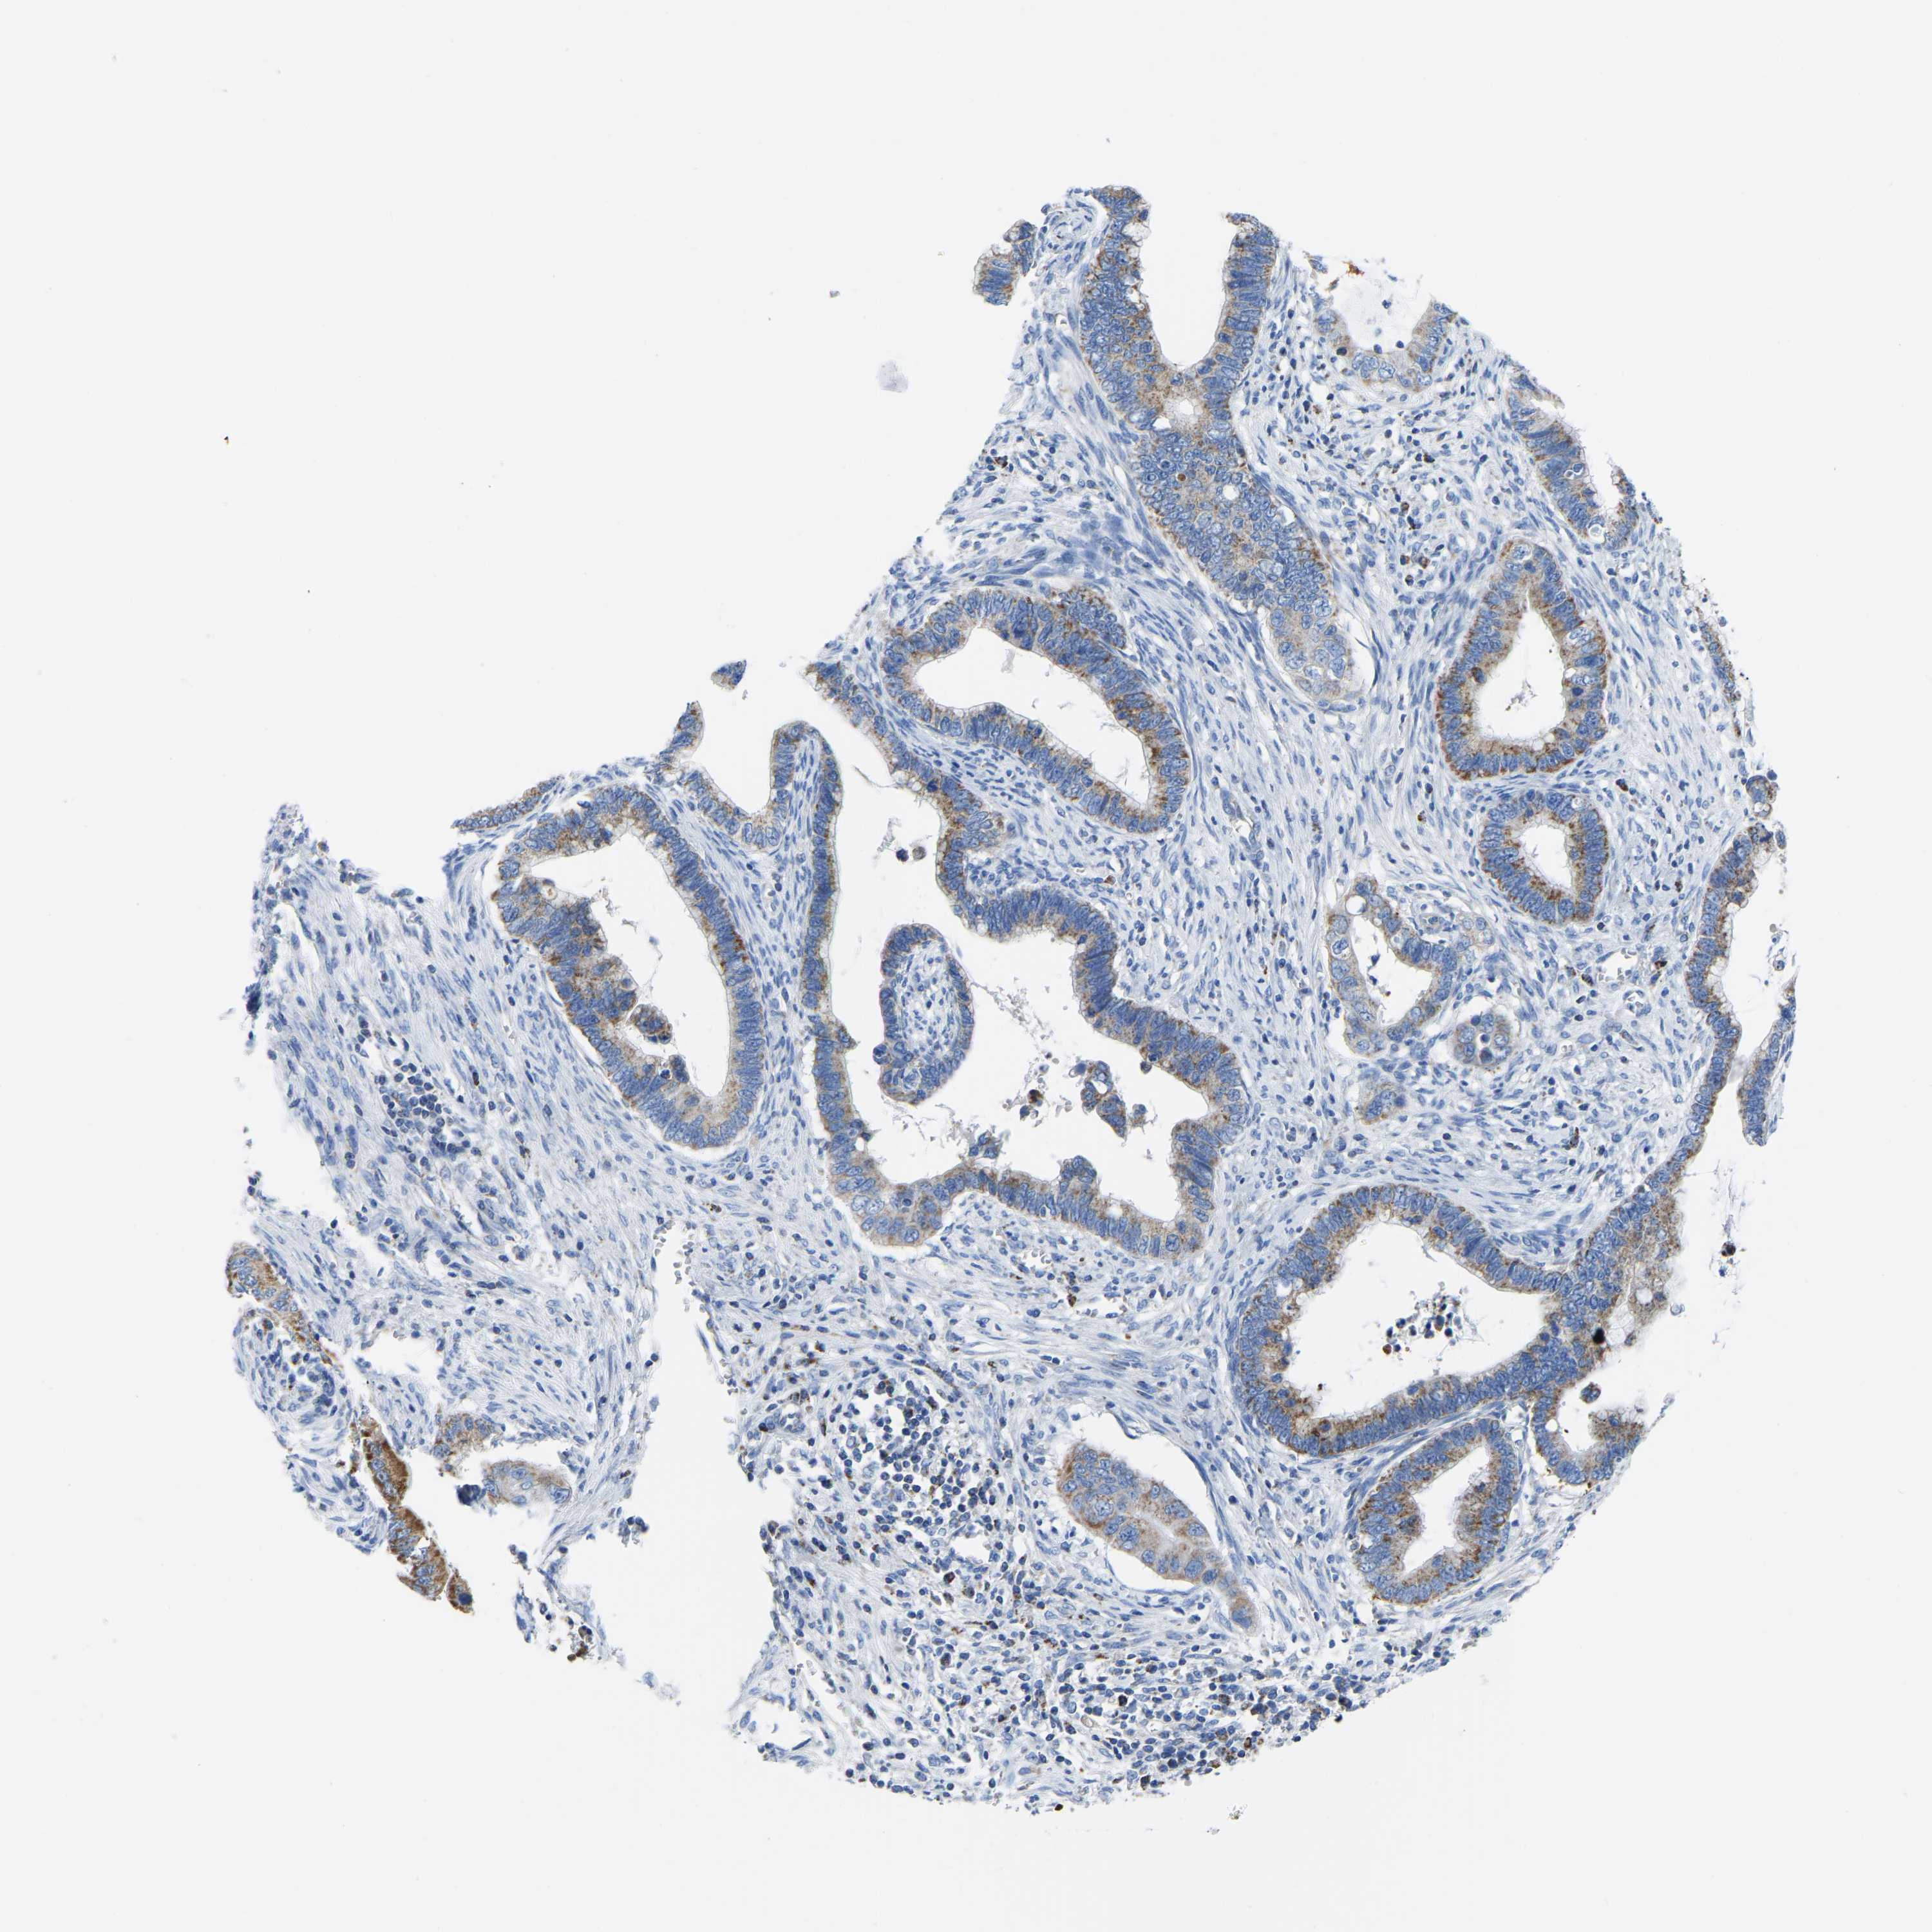

CERVICAL CANCER - Protein expressioni

A mouse-over function shows sample information and annotation data. Click on an image to view it in a full screen mode. Samples can be filtered based on level of antibody staining by selecting one or several of the following categories: high, medium, low and not detected. The assay and annotation is described here.

Note that samples used for immunohistochemistry by the Human Protein Atlas do not correspond to samples in the TCGA dataset.

Antibody stainingi

Antibody staining in the annotated cell types in the current human tissue is reported as not detected, low, medium, or high, based on conventional immunohistochemistry profiling in selected tissues. This score is based on the combination of the staining intensity and fraction of stained cells.

Each image is clickable and will lead to virtual microscopy that enables deeper exploration of all samples and also displays staining intensity scores, fraction scores and subcellular localization as well as patient and tissue information for each sample.

Antibody HPA018990

Antibody HPA018993

Antibody HPA018996

Antibody HPA024089

Staining

High

Medium

Low

Not detected

Intensity

Strong

Moderate

Weak

Negative

Quantity

>75%

75%-25%

<25%

None

Location

Nuclear

Cytoplasmic/membranous

Cytoplasmic/membranous,nuclear

Squamous cell carcinoma, NOS

Adenocarcinoma, NOS